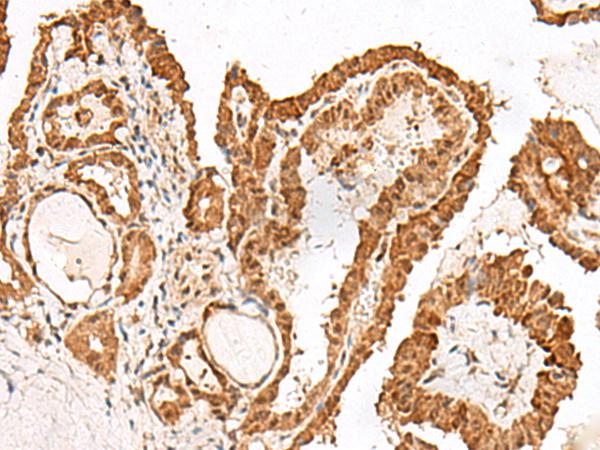

IHC positive control:

Human esophagus cancer and Human thyroid cancer

IHC Recommend dilution:

50-300